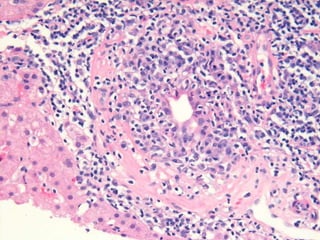

BS08-12291 36 yo, female.  Clinical history:  AMA 1:1280, rule out PBC.

BS08-12291 Dx: Primary biliary cirrhosis (diagnostic biopsy), Scheuer stage 2/4; cannot exclude overlap autoimmune hepatitis. Comment: Bile duct paucity and active, diagnostic duct destructive lesions are identified.  Some portal tracts are expanded by a prominent ductular reaction.  Significant scarring is not seen.  The degree of interface and lobular hepatitis is focally more severe than is typical for primary biliary cirrhosis and suggests the possibility of overlap autoimmune hepatitis; clinical correlation required.

BS08-12291 36 yo,female. Clinical history: AMA 1:1280, rule out PBC.

BS08-12291 Dx: Primarybiliary cirrhosis (diagnostic biopsy), Scheuer stage 2/4; cannot exclude overlap autoimmune hepatitis. Comment: Bile duct paucity and active, diagnostic duct destructive lesions are identified. Some portal tracts are expanded by a prominent ductular reaction. Significant scarring is not seen. The degree of interface and lobular hepatitis is focally more severe than is typical for primary biliary cirrhosis and suggests the possibility of overlap autoimmune hepatitis; clinical correlation required.